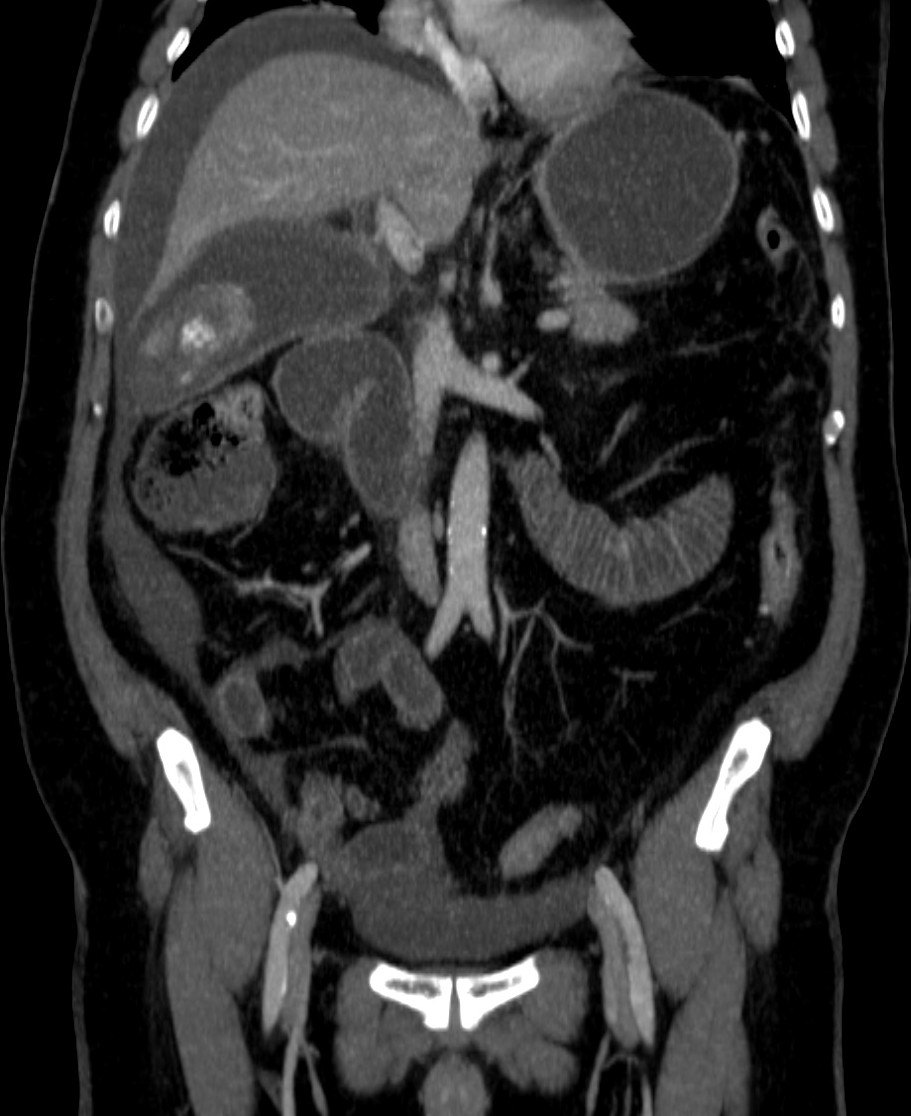

Se realizó posteriormente TC abdominal por mala evolución del paciente:

– La TC se reserva para pacientes con dudas diagnósticas o con discrepancia clínico ecográfica. Se obervarán los mismos hallazgos que en la ecografía, además del aumento de densidad de la pared de la vesícula, del parénquima hepático o especialmente la presencia de otras complicaciones.

- Colecistitis xantunogranulomatosa: nódulos o bandas intramurales. Se producen por la oclusión de los senos de Rokitansky Aschoff de la pared, los cuales se rompen, luego la bilis coloniza la pared y finalmente produce una reacción inflamatoria a la que puede sobreañadirse una infección. Es un factor de riesgo para el carcinoma.

- Eco y TC: Litiasis + engrosamiento mural focal o difuso. Puede haber cambios inflamatorios pericolecísiticos. Los nódulos hipocogénicos o bandas pueden sugerir el diagnóstico específico de c. xantunogranulomatosa.

- El diagnóstico raramente se realiza previo a la cirugía y al análisis histopatologíco.